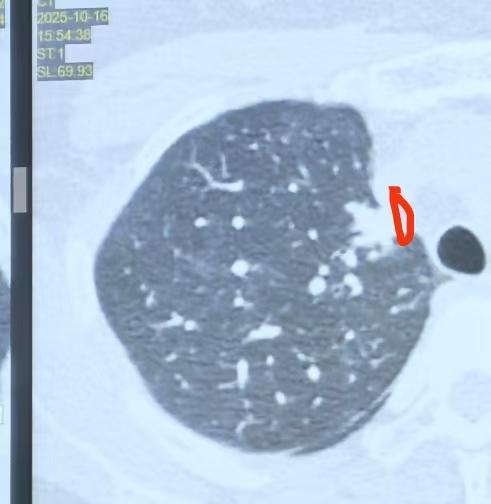

经常有朋友问我:手术医生说有胸膜侵犯了,但病理报告里却没有提到胸膜侵犯,到底应该以什么为标准?术后还需不需要治疗? 今天这台手术,是一个实性结节,结节紧贴胸膜。我手术中看到肿瘤在胸膜上有皱缩,颜色发白。但我们在冰冻病理下看到的胸膜是完整的。 我给大家讲一下,胸膜侵犯是怎么判断的!(图3)黑黑的都是癌细胞,而这边粉红色的结构就是胸膜。可以看到,肿瘤并没有穿透胸膜,有些地方胸膜虽然变薄,但整体是完整的。冰冻病理显示胸膜仍然完整,没有完全穿透,只是贴得非常近。 所以,尽管我们肉眼看到胸膜有皱缩,可能表面凹凸不平,但肿瘤并没有穿出来。这就好比胸膜是“长城”,肿瘤还在里面,没有突破出来。 这种情况就不算扩散,也就是病理学上判断胸膜是否被侵犯的标准——肿瘤没有侵犯胸膜。 当然,冰冻病理并非百分之百准确,我们还要等待常规病理和免疫组化染色的结果。实际上,冰冻病理的准确率大概在百分之七八十左右。 目前看到的是肿瘤没有突破胸膜,我认为即使最终确认有胸膜侵犯,也很可能是PL1这种未突破的类型(图4),预后会比PL2、PL3好很多,甚至完全不同。 因此,胸膜侵犯的判断,最终还是要以病理显微镜下的结果为准。[谢谢][玫瑰]